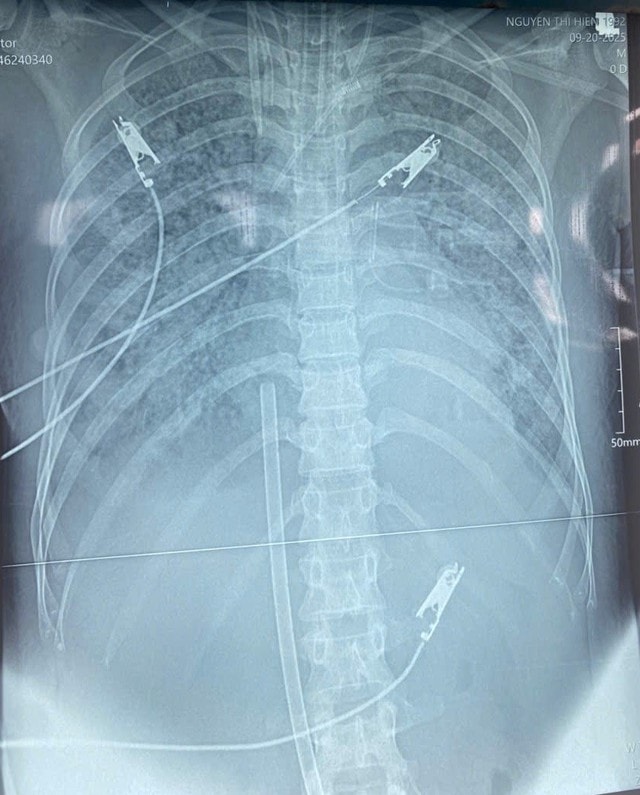

Trước đó, bệnh nhân N.T.H. (37 tuổi, ở Nghệ An) được người nhà đưa đến Bệnh viện trong tình trạng suy hô hấp cấp, thở nhanh co kéo, khó thở, chỉ số SpO₂ (độ bão hòa oxy máu ngoại vi) chỉ đạt 70%, phổi ran nổ nhiều hai bên. Bệnh nhân được chuyển Khoa Hồi sức tích cực với chẩn đoán sốc nhiễm trùng, viêm phổi biến chứng ARDS mức độ nặng, tổn thương cơ tim cấp, suy đa tạng.

Các bác sĩ Khoa Hồi sức tích cực đã quyết định triển khai kỹ thuật tim phổi nhân tạo ECMO – giải pháp được coi là "cứu cánh cuối cùng" trong hồi sức. Điểm đặc biệt của ca bệnh là bệnh nhân vừa huyết áp thấp dù đã sử dụng ba vận mạch, trợ tim phối hợp liều cao, vừa suy hô hấp rất nặng. Do đó, một chế độ ECMO đơn thuần không thể đáp ứng. Các bác sĩ đã lựa chọn Hybrid ECMO (V-A-V ECMO) – sự kết hợp đồng thời giữa VV-ECMO và VA-ECMO, vừa hỗ trợ hô hấp, vừa hỗ trợ tuần hoàn.

Song song với VAV ECMO, bệnh nhân còn được phối hợp nhiều biện pháp điều trị tích cực như thở máy xâm nhập, lọc máu liên tục, lọc máu hấp phụ cytokine, chống đông, kháng sinh phổi hợp và tối ưu theo kháng sinh đồ, dự phòng loét ép, tập phục hồi chức năng hô hấp, hỗ trợ dinh dưỡng toàn diện, góp phần ổn định dần sức khỏe.